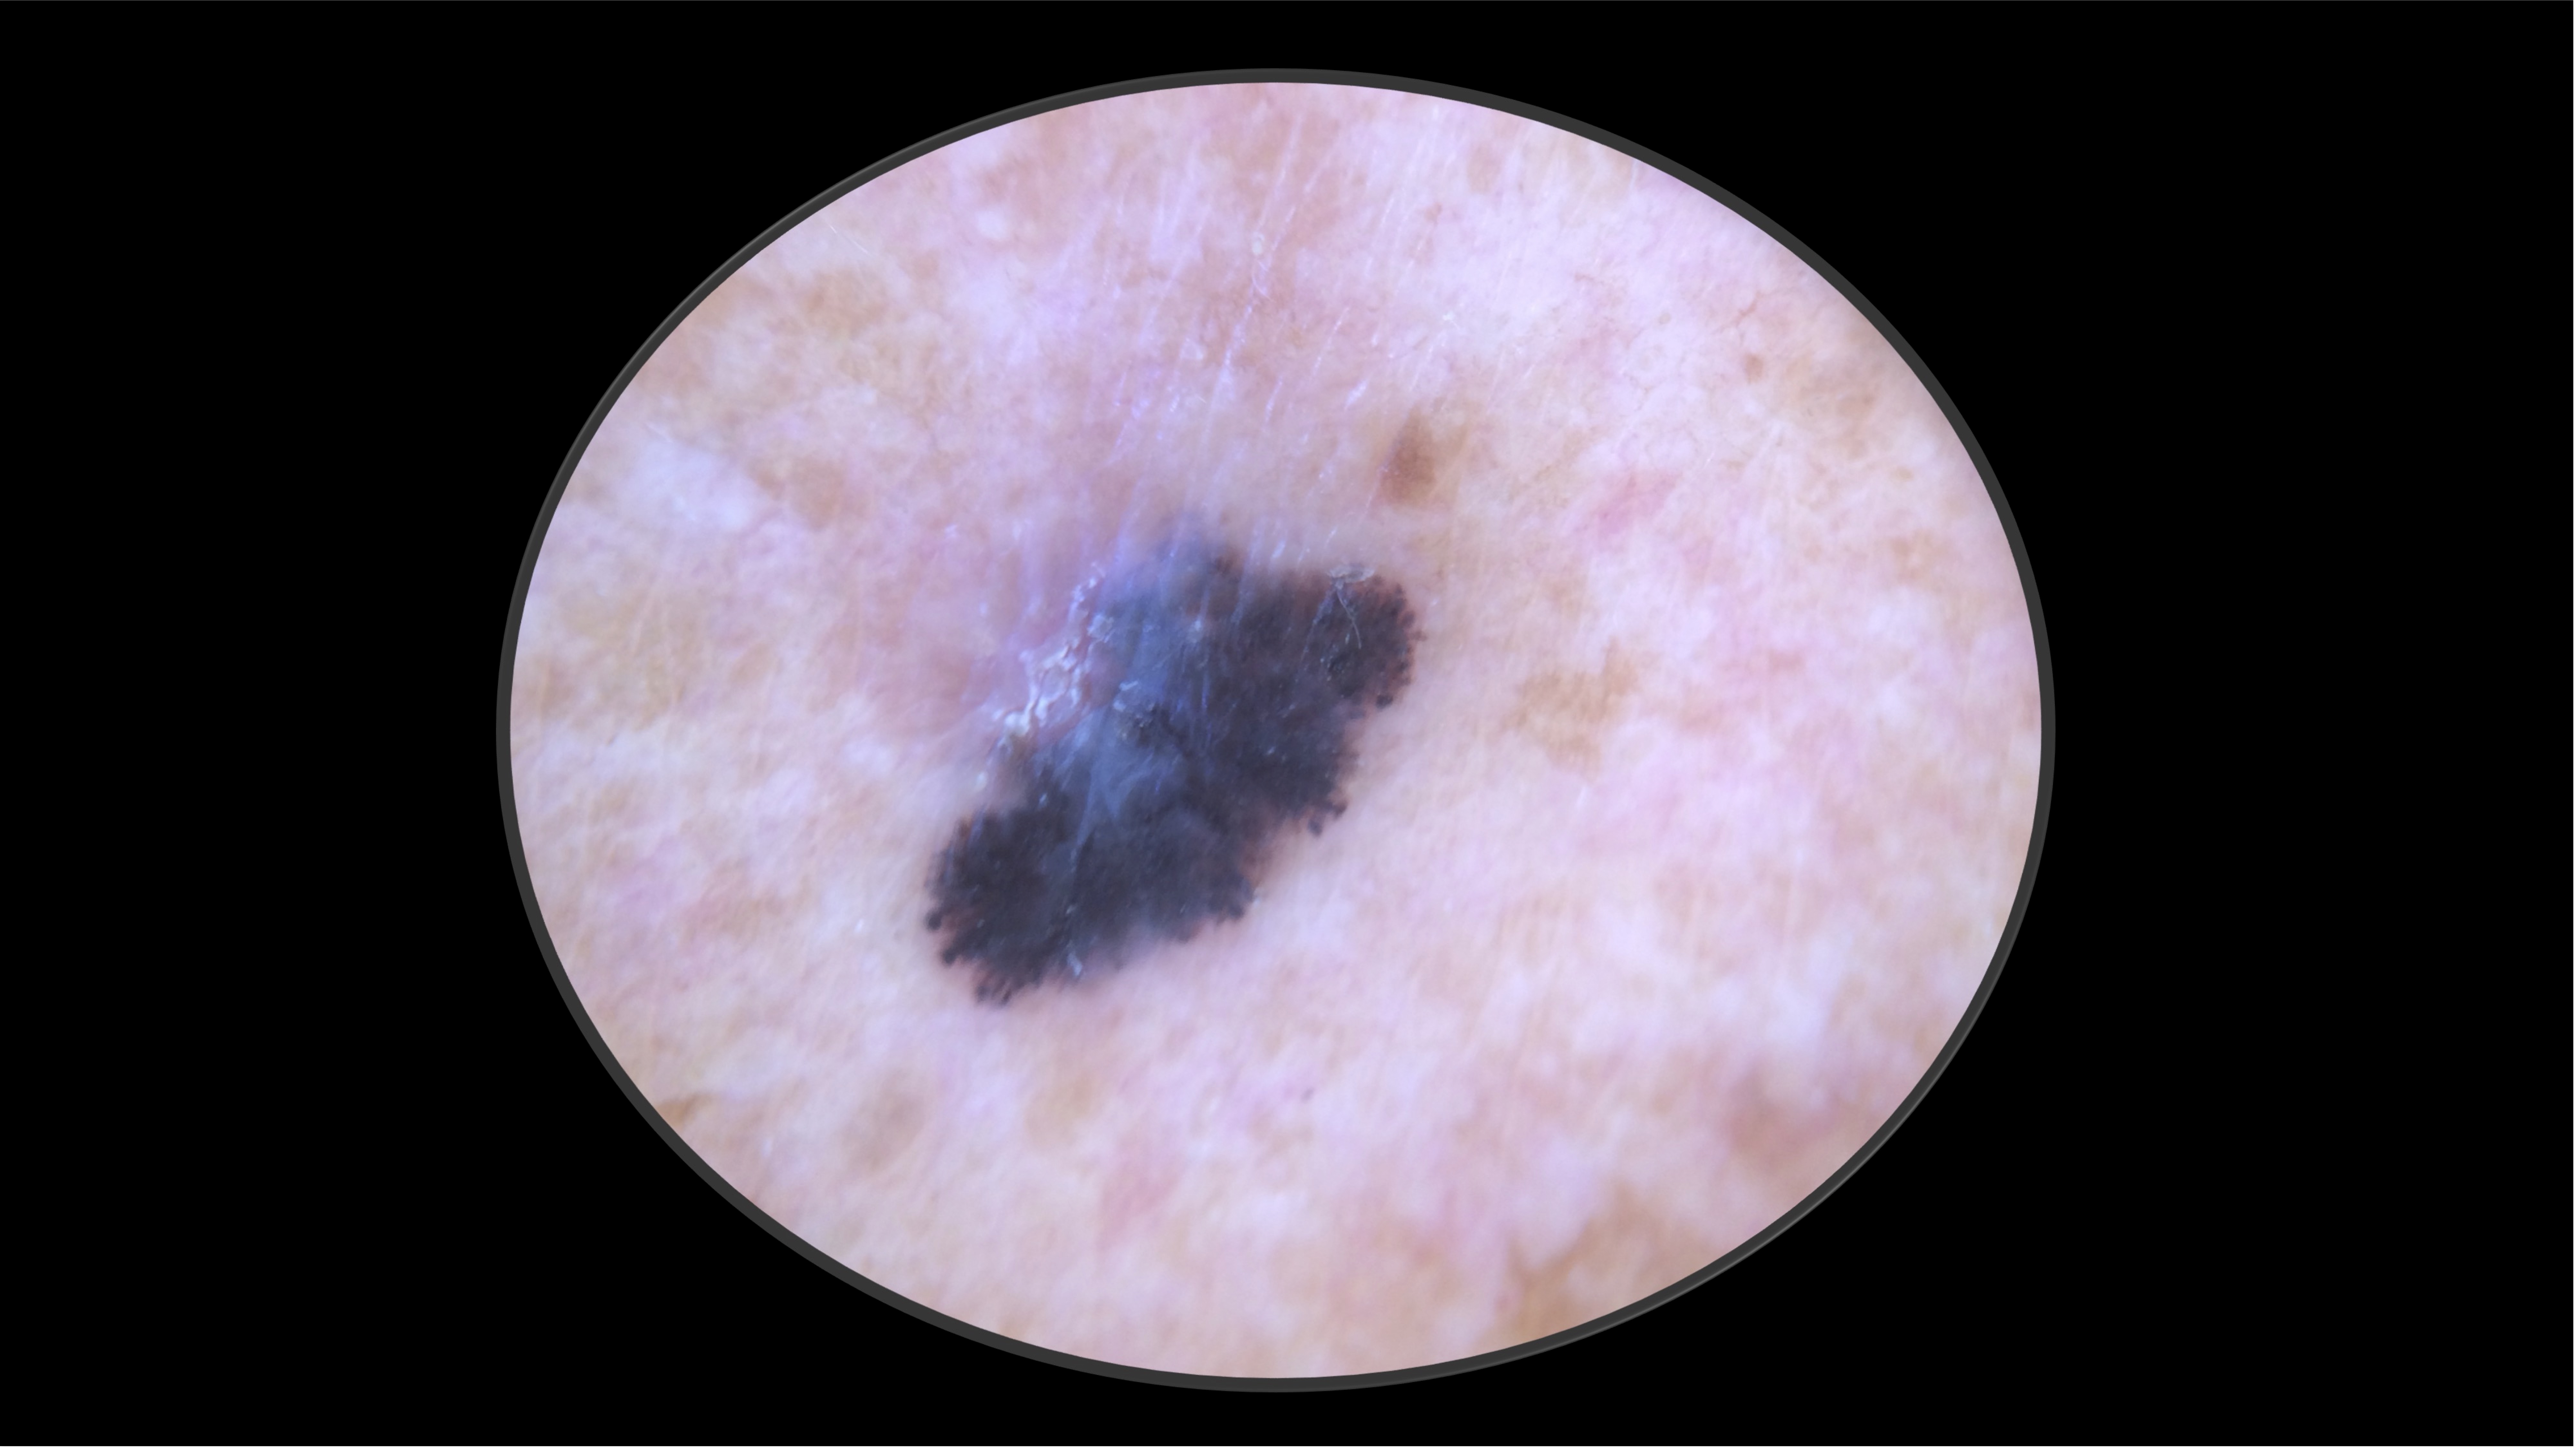

71-year-old Fitzpatrick skin type 2 male with no significant PMH presents with this lesion on his chest x 3 months

Case 2 - Work Up

- Excisional biopsy performed.

- Pathology revealed a 4.1 mm thick, non-ulcerated, superficial spreading melanoma. Mitotic rate 9 per mm2. LVI present. Tumor infiltrating lymphocytes present, non-brisk. No microsatelites.

- Subsequent PET-CT and brain MRI demonstrated no regional or distant metastases.